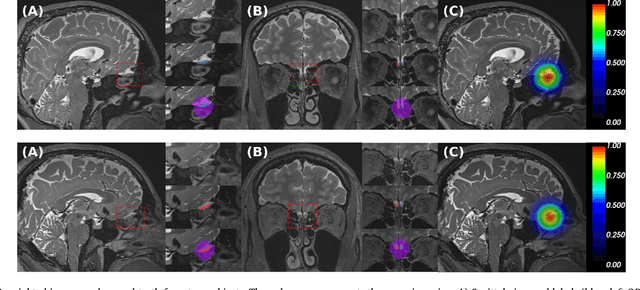

Abstract:The neuroimage analysis community has neglected the automated segmentation of the olfactory bulb (OB) despite its crucial role in olfactory function. The lack of an automatic processing method for the OB can be explained by its challenging properties. Nonetheless, recent advances in MRI acquisition techniques and resolution have allowed raters to generate more reliable manual annotations. Furthermore, the high accuracy of deep learning methods for solving semantic segmentation problems provides us with an option to reliably assess even small structures. In this work, we introduce a novel, fast, and fully automated deep learning pipeline to accurately segment OB tissue on sub-millimeter T2-weighted (T2w) whole-brain MR images. To this end, we designed a three-stage pipeline: (1) Localization of a region containing both OBs using FastSurferCNN, (2) Segmentation of OB tissue within the localized region through four independent AttFastSurferCNN - a novel deep learning architecture with a self-attention mechanism to improve modeling of contextual information, and (3) Ensemble of the predicted label maps. The OB pipeline exhibits high performance in terms of boundary delineation, OB localization, and volume estimation across a wide range of ages in 203 participants of the Rhineland Study. Moreover, it also generalizes to scans of an independent dataset never encountered during training, the Human Connectome Project (HCP), with different acquisition parameters and demographics, evaluated in 30 cases at the native 0.7mm HCP resolution, and the default 0.8mm pipeline resolution. We extensively validated our pipeline not only with respect to segmentation accuracy but also to known OB volume effects, where it can sensitively replicate age effects.